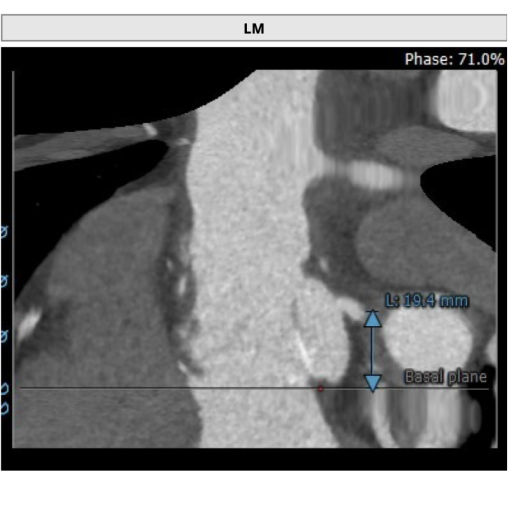

左冠高度:19.4mm,右冠高度:18.4mm